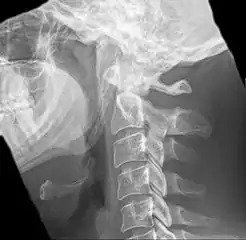

| Anteroposterior and lateral radiographs of cervical spine showing ossification of the stylohyoid ligament on both sides | |

Radiograph, lateral view showing elongated stylohyoid process and stylohyoid ligament ossification

Radiograph, lateral view showing joint-like formation in ossified stylohyoid ligament

Imaging is important and is diagnostic. Visualizing the styloid process on a CT scan with 3D reconstruction is the suggested imaging technique.[11] The enlarged styloid may be visible on an orthopantogram or a lateral soft tissue X ray of the neck.